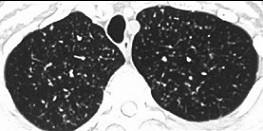

- 单项选择题女,23岁, 消瘦盗汗1月余,干咳1周, 偶痰中带血,影像如图, 最可能的诊断为 ( )

A、粟粒性肺结核

B、含铁血黄素沉着

C、弥漫性肺纤维化

D、慢性支气管炎

E、SLE肺部侵犯